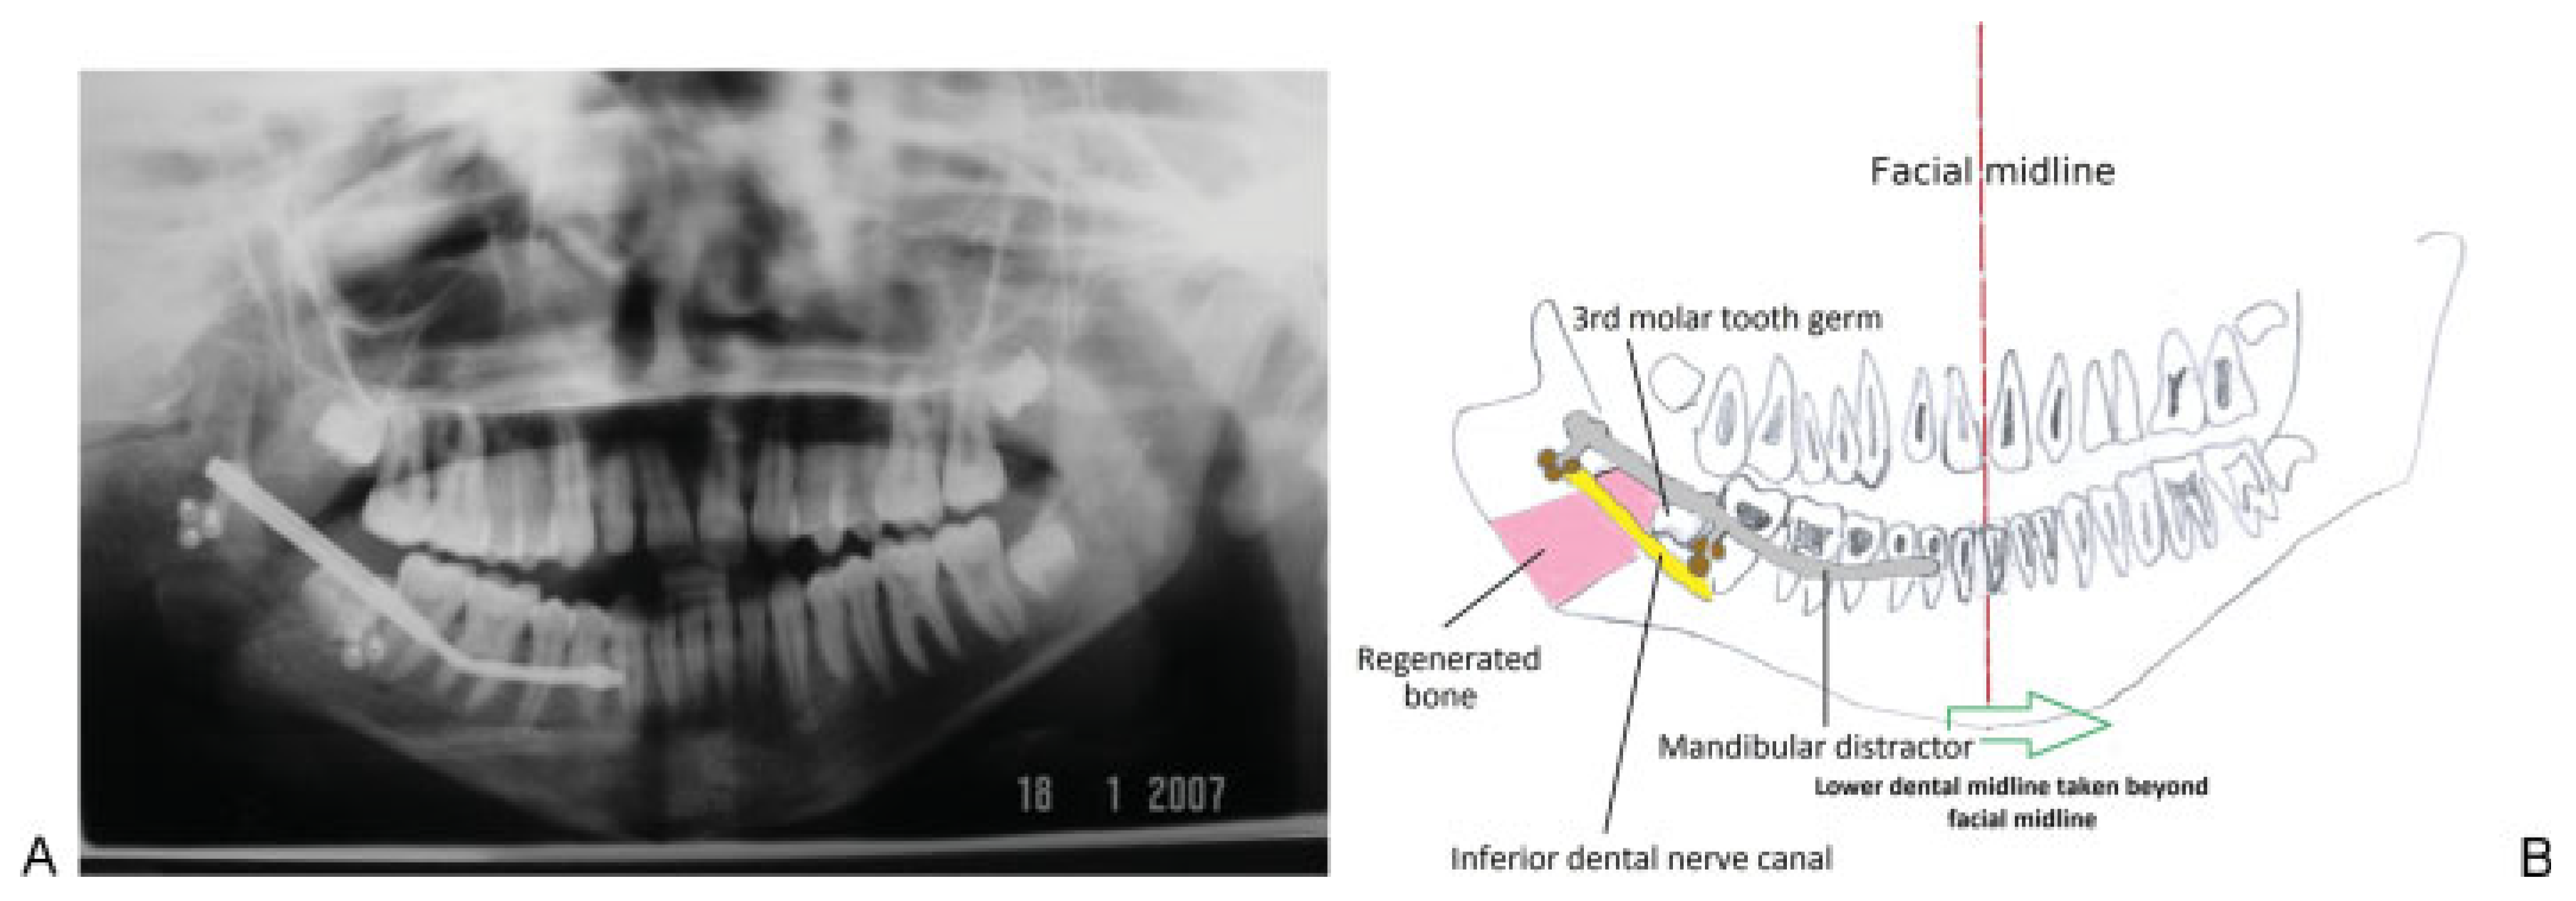

Figure 13. (A) A postmandibular distraction osteogenesis orthopantomogram. (B) Schematic diagram of anatomical structures on conclusion of distraction osteogenesis. The lower dental midline has been taken beyond the facial midline (interrupted red line) to allow for possible relapse. The pink shaded area represents regenerated bone formed as a result of distraction osteogenesis.

Preoperative assessment of the mandible prior to making the osteotomy cuts and placement of the distractor was assisted by the use of an OPG. The osteotomy cuts (Figure 11) have been previously described [3,4].

A Zurich Pediatric Ramus Distractor (KLS Martin®, Tuttlingen, Germany) was placed across the osteotomy site. Distraction was achieved by turning the distractor rod with a screwdriver. Each turn represented 0.5-mm movement. The rod was turned twice daily. Progress with distraction was monitored both radiographically and clinically. Serial OPGs were used to radiographically follow progress.

Clinical evaluation consisted of watching for improvements in both the dental and facial midlines and whether the mandibular deviation associated with mouth opening improved. On completion of distraction, a post mandibular distraction osteogenesis OPG was taken (Figure 13A). In anticipation of continued growth from the unaffected side and possible relapse, mandibular distraction was continued beyond the dental midline (Figure 13B).